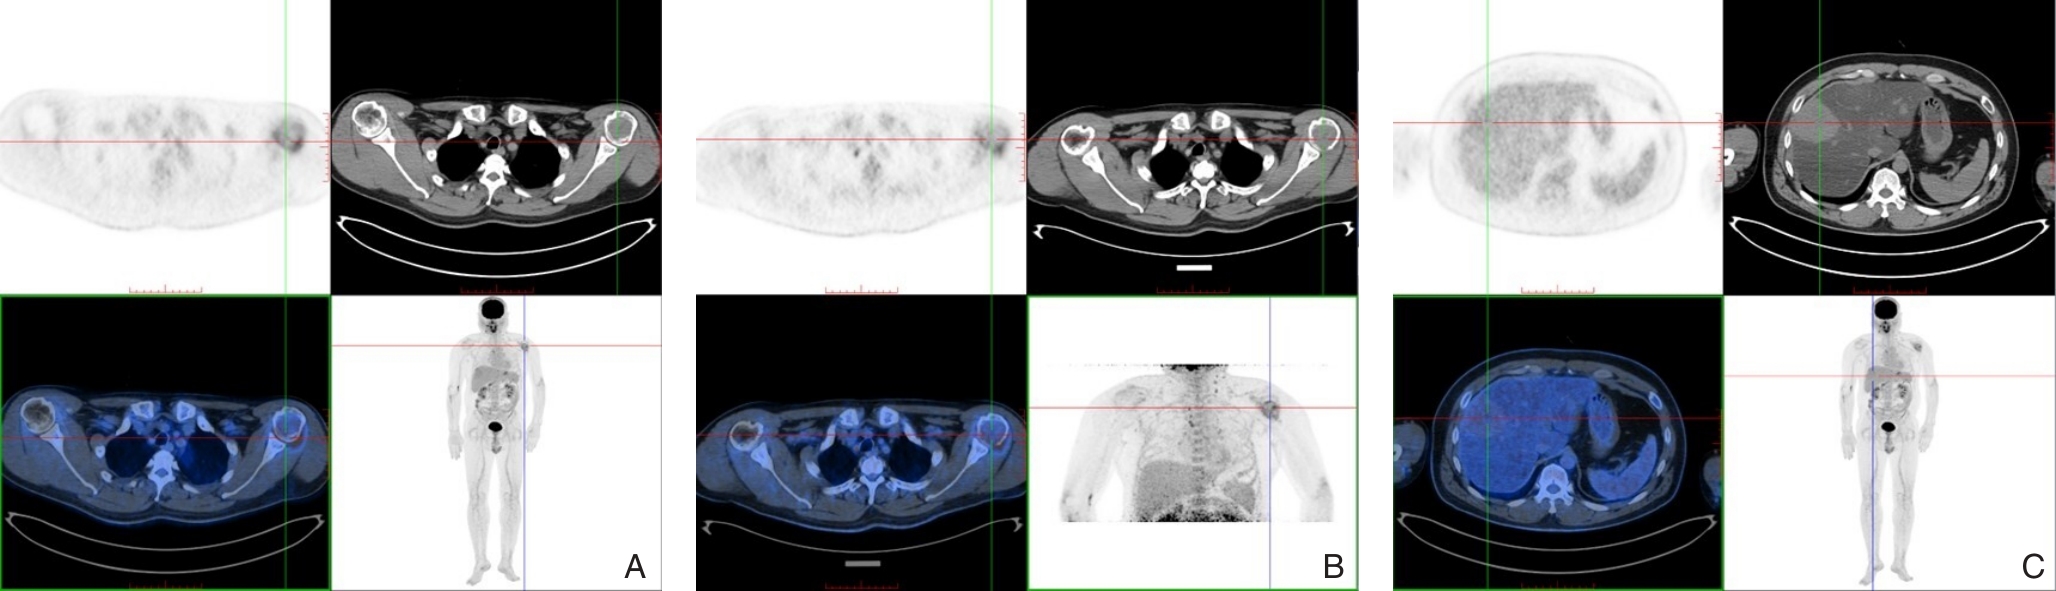

2026, 35(1):141-148. DOI: 10.7659/j.issn.1005-6947.250622

Abstract (79) HTML (119) PDF 1.24 M (183) Comment (0) Favorites

Abstract:Background and Aims Hepatocellular carcinoma (HCC) presenting initially with bone metastasis is uncommon, and metastasis to the appendicular skeleton is particularly rare. These cases often lack typical liver disease history, elevated alpha-fetoprotein (AFP), or characteristic imaging findings, leading to frequent misdiagnosis or delayed diagnosis. This study reports a rare case of occult HCC presenting with humeral metastasis and reviews the literature to improve clinical recognition and management.Methods The clinical data of a 42-year-old male patient presenting with humeral metastasis as the initial manifestation admitted in August 2025 were retrospectively analyzed, including laboratory tests, multimodal imaging findings, histopathological and immunohistochemical results, treatment, and follow-up outcomes. Relevant literature was also reviewed.Results The patient presented with left shoulder pain. Imaging revealed osteolytic destruction of the left humerus. PET/CT incidentally detected multiple hepatic lesions without significant FDG uptake. Contrast-enhanced ultrasound demonstrated atypical enhancement patterns, initially suggesting a perivascular epithelioid cell tumor. Histopathological and immunohistochemical examination of biopsy specimens from both the humeral and hepatic lesions confirmed moderately differentiated hepatocellular carcinoma with humeral metastasis (CNLC stage IIIb). The patient received systemic therapy with sintilimab plus bevacizumab, followed by transcatheter arterial chemoembolization. After 6 months of follow-up, the intrahepatic lesions had decreased in size, the bone metastasis remained stable, and pain symptoms were significantly relieved.Conclusion HCC presenting with humeral metastasis as the initial manifestation is extremely rare and may lack typical imaging and serological features. Clinicians should consider HCC in patients with unexplained bone metastasis even in the absence of liver disease history or elevated AFP. Multimodal imaging and pathological biopsy are essential for accurate diagnosis and appropriate management.